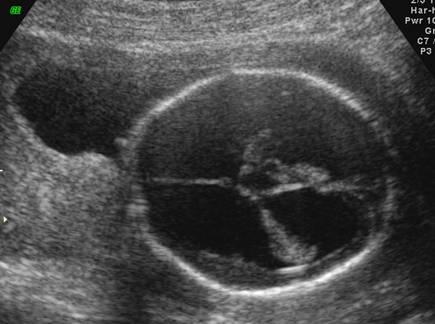

What is the function of the choroid plexus?

produce cerebrospinal fluid

Choroid Plexus

What is the size of the choroid plexus at 20 week scan?

10 mm or less

Why is the choroid plexus image taken?

to exclude ventricular megaly

What is a dangling choroid plexus caused by?

ventricular megaly

dangling choroid plexus